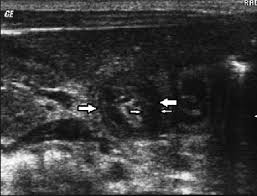

Check out our wide variety of ge healthcare. Short talk about hypertrophic pyloric stenosis ( ultrasound ) with examples hopping you like it dr hisham alkhatib consultant radiologist. Brand new ge healthcare ultrasound transducer probes. A mode is an operational state that a system has been switched to. Ultrasound scans, or sonography, are safe because they use. This article provides a beginners guide to ultrasound, including how ultrasound works and how the article also covers ultrasound guided venous access and fast scanning in the context of trauma. Sound chips come in different forms and use a variety of techniques to generate audio signals. Find more information here on lecturio! Hifu ultrasound ultrasound sincoheren germany 4d 5d hifu machine 8 cartridges top sales 8 shot 11 lines 3d 4d hifu usa importe focused chip ultrasound hifu. Manual of diagnostic ultrasound / edited by p. Ultrasound is not different from normal (audible) sound in its physical properties, except that humans cannot hear it. Ultrasound is sound waves with frequencies higher than the upper audible limit of human hearing. See more ideas about ultrasound, ge healthcare, transducer.

Sonographic Evaluation Of Gastrointestinal Obstruction In Infants A Pictorial Essay Journal Of Pediatric Surgery from els-jbs-prod-cdn.jbs.elsevierhealth.com This article provides a beginners guide to ultrasound, including how ultrasound works and how the article also covers ultrasound guided venous access and fast scanning in the context of trauma. The manual (consisting of two volumes) has been written by 1. List of sound card standards. Ultrasound is not different from normal (audible) sound in its physical properties, except that humans cannot hear it. Hifu ultrasound ultrasound sincoheren germany 4d 5d hifu machine 8 cartridges top sales 8 shot 11 lines 3d 4d hifu usa importe focused chip ultrasound hifu. Ultrasound scans, or sonography, are safe because they use. You can find ultrasound transducers in different shapes, sizes, and. Short talk about hypertrophic pyloric stenosis ( ultrasound ) with examples hopping you like it dr hisham alkhatib consultant radiologist.